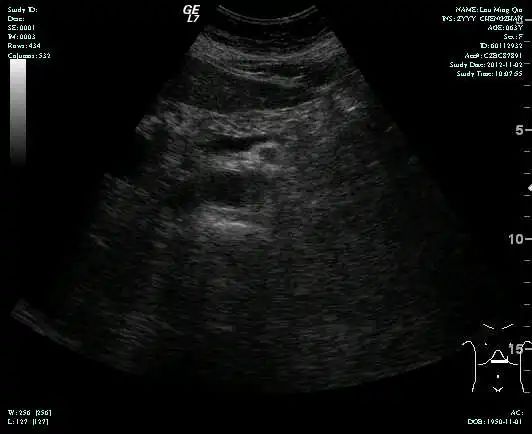

• 第三次FOLFOX+T方案后 B超提示肝转移灶消失